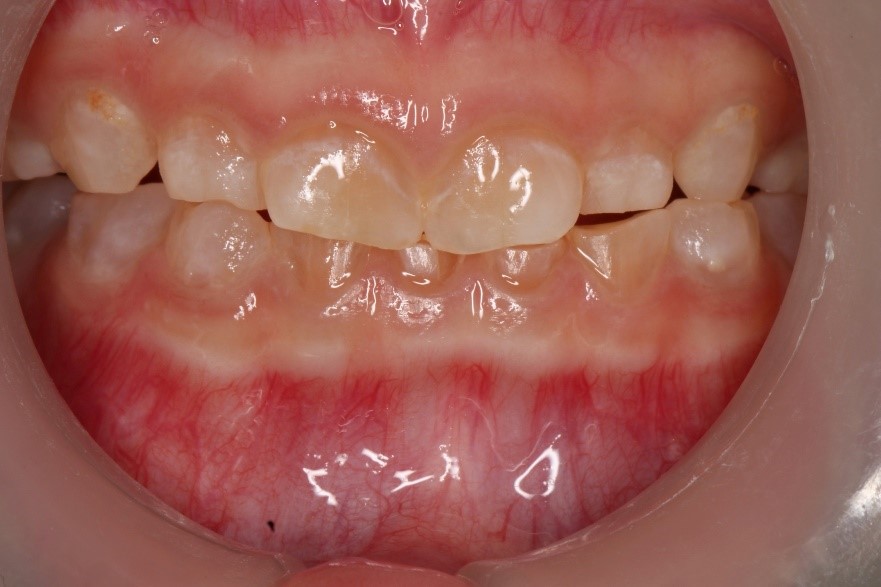

Dentinogenesis imperfecta-Type I (DGI-Type I) is a dental developmental anomaly observed in some osteogenesis imperfecta (OI) patients. Teeth in this dental anomaly often appear discoloured, and their enamel breaks easily due to the defective underlying dentine. The affected teeth are abraded rapidly if the condition is not identified early. Early diagnosis allows the proper execution of age-based preventive and rehabilitation strategies. Protection of the affected teeth enables various functions of the dentition, such as mastication and dental aesthetics, which could be maintained effectively in growing OI children. Thus ensuring the oral health-related quality of life of the patients with OI is at par with that of their healthy counterparts.

Anterior view of the dentition before treatment